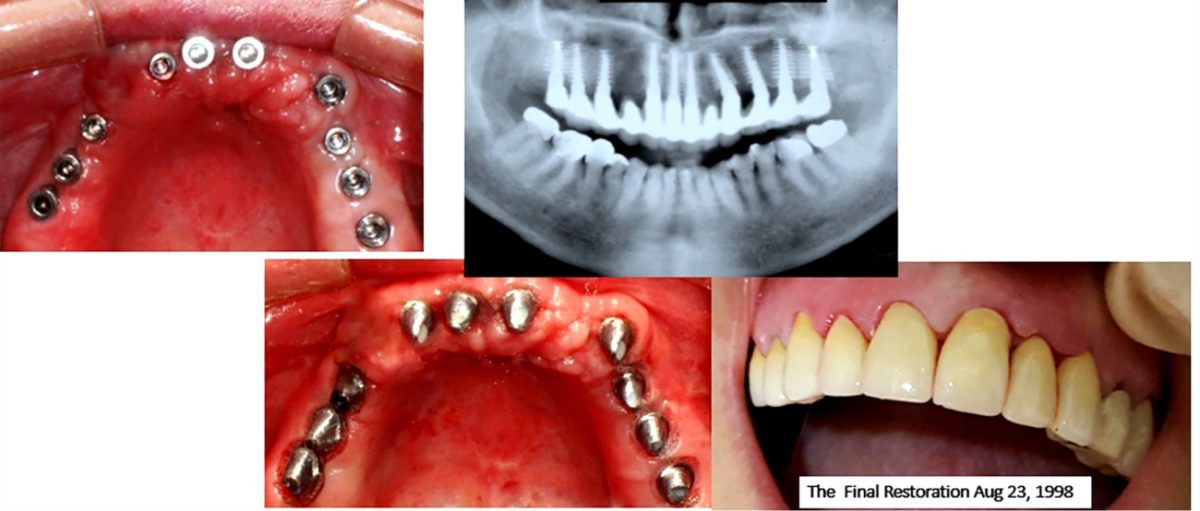

The author presents a 15-year retrospective study of 1957 that immediately placed implants in fresh extraction sites. The extraction sites were developed into sockets soon after the atraumatic extractions by our osseo-manipulation techniques. The protocol used is described here for the understanding of the original technique which was developed by the author in 2009 for the placement and restoration of implants back to their original 3-D engineered Divine osseo-architecture, the ‘‘SABIRIN’’ -Stable Alveolar Bone Implant Reconstructive Integration Naturally. ‘‘SABIRIN’’ is achieved by a special design of instruments for bone manipulation [1] [2] which are used in a progressive and codified manner thereby resulting in the reversal of the atrophic bone & overlying soft tissues. This is accomplished by the amalgamation of varied autologous growth factors, which are used to have a long-term success & unparalleled aesthetic predictability.

The osseo-manipulation technique is a significant advancement in attaining the reconstructive integration of the stable alveolar bone with an implant. This is an atraumatic, flapless surgical technique for treating the thin ridges (up to 1mm) to develop the most desirable width of bone to receive an implant of natural diameter. It facilitates alveolar ridge expansion with appropriate armamentaria, implants & preserves the bone, enhances the healing, and increases the bone quality & quantity. The osseo-manipulation and densification [3] is performed by utilizing the om® system in a progressive fashion with specially designed osseo-manipulation instrumentation, (MQI-patented osseo-manipulation drills kit Art# MQI14485), resulting in reversal of the atrophic bone & overlying soft tissues back to their natural 3-D shape, dimensions, and unsurpassed aesthetics.

Conclusion: The osseo-manipulation technique stands at the forefront of implant dentistry, representing a transformative leap towards predictable outcomes and heightened patient satisfaction. By meticulously preserving bone and soft tissue integrity, minimizing surgical trauma, and enabling immediate loading, this technique addresses the escalating demand for efficient and aesthetically pleasing implant solutions. Throughout our study, we utilized a diverse array of implants and systems featuring varying diameters, lengths, shapes, and surface characteristics. Incorporating both immediate provisionalization and loading strategies, we achieved an impressive average survival rate nearing 95%. Compared to traditional bone grafting methods and surgical guides, osseo-manipulation demonstrates superior prognosis and outcomes. It fosters the development of stable bone quality, supporting natural implant positions with harmonious emergence profiles. This approach ensures consistent aesthetics, reduces complication risks by eliminating foreign grafts, and significantly shortens treatment times, thereby lowering overall costs for patients.

Key factors contributing to this stability include the maintenance of expanded alveolar bone integrity, uninterrupted blood supply, contamination-free biologic width around trans-mucosal implants, enhanced surface area for optimal bone loading, increased bone thickness, stable gingival health, non-pathological occlusion, and patient adherence to post-operative care.